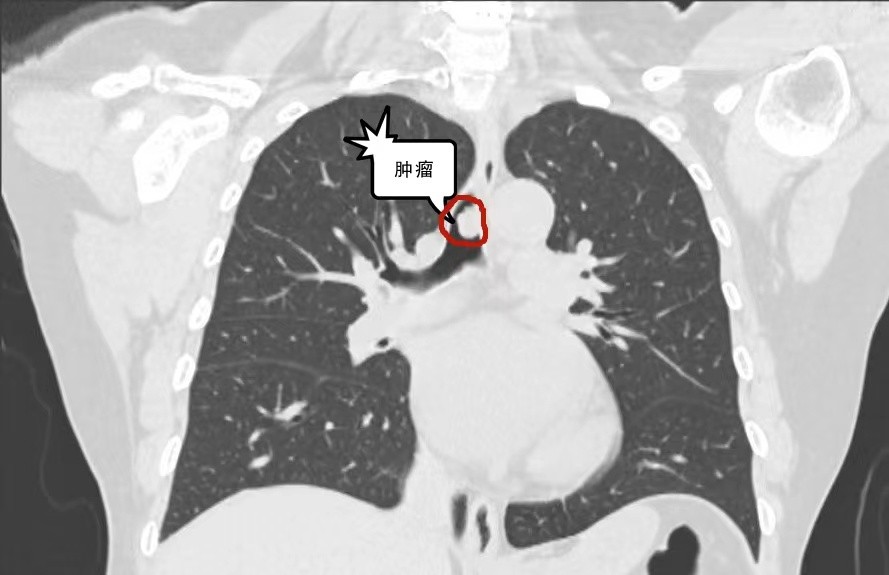

为了彻底查明自己的身体状况,熊阿姨在当地医院进行了详尽的胸部CT检查。检查结果显示——她的气管内竟然长了一个瘤体,已经堵塞了气道近半的空间。当地医院医生在全面评估了熊阿姨的病情后,深感其复杂性与严峻性,为了确保最佳的治疗效果,建议熊阿姨转往大医院进一步诊治。在武汉的大医院,熊阿姨接受了一系列针对性的治疗:首先是通过支气管动脉栓塞术,试图阻断为瘤体提供血液营养的血管,以遏制其生长;随后,又进行了气管镜下高配电圈套结合冷冻治疗,直接对气管内的肿瘤进行了精准切除。这一系列治疗初期效果显著,熊阿姨的咳嗽、咳痰等症状得到了明显缓解。

然而,好景不长,仅仅两周之后,熊阿姨再次出现咳嗽、咳痰以及痰中带血的症状。复查胸部CT,显示瘤体不仅重新在原位置生长,而且体积比之前更大,气道已被堵塞至三分之二,情况危急,若不及时控制,熊阿姨的生命将面临窒息死亡的严重威胁!

入院后,蔡松旺主任团队对熊阿姨的病情进行了全面评估,并重新进行了纤支镜检查。检查结果显示,肿瘤位于气管分叉上方,已堵塞超过80%的气道,导致血氧饱和度降至85%。